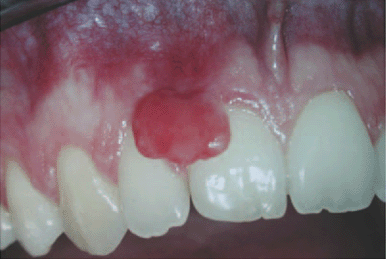

Pyogenic granuloma is a common tissue tumor, which affects up to 10% of pregnant women. It is an overgrowth of tissue due to irritation, trauma, or hormonal factors. This granuloma may be red, pink, or purple, growing rapidly. It may be smooth or mushroom-shaped and commonly seen on the labial surface of the papilla. Newer lesions appear red due to the abundance of blood vessels, and older lesions are pinker. During the first trimester up into the seventh month are when the lesions are most likely to occur.5

Pregnancy epulis is termed the “pregnancy tumor” since it occurs exclusively in pregnant women. The developed epulis (an enlargement on the gingival or alveolar mucosa) surfaces from hormonal changes and an increased inflammatory response to plaque or other irritants. This nonpainful, benign tumor is made up of capillary vessels and endothelial proliferation. It tends to bleed easily and appears red and inflamed.

The epulus appears mostly in the maxillary anterior region (see Figure 1). There is usually pregnancy gingivitis involved and commonly appears in the third trimester of pregnancy in up to 5% of pregnant women. After birth, it decreases or disappears.4,5